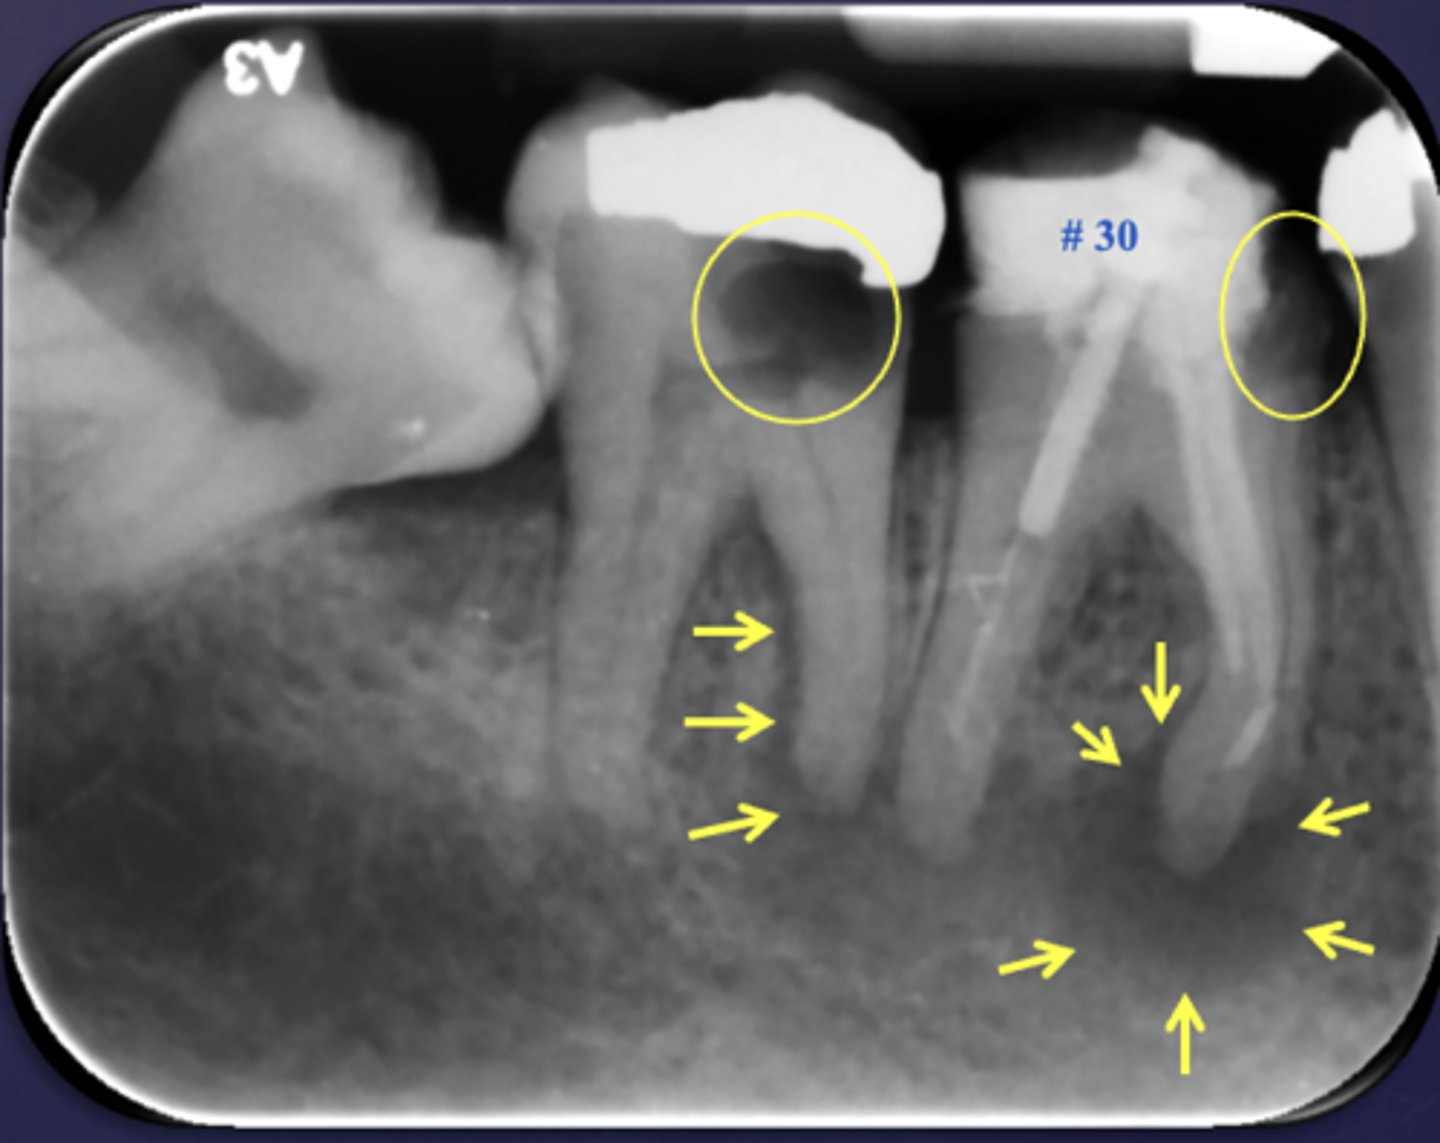

What are the arrows pointing to?

halo sign

periostitis/onion skin

Periostitis and mucositis

What condition?

maxillary sinus floor periostitis/mucositis